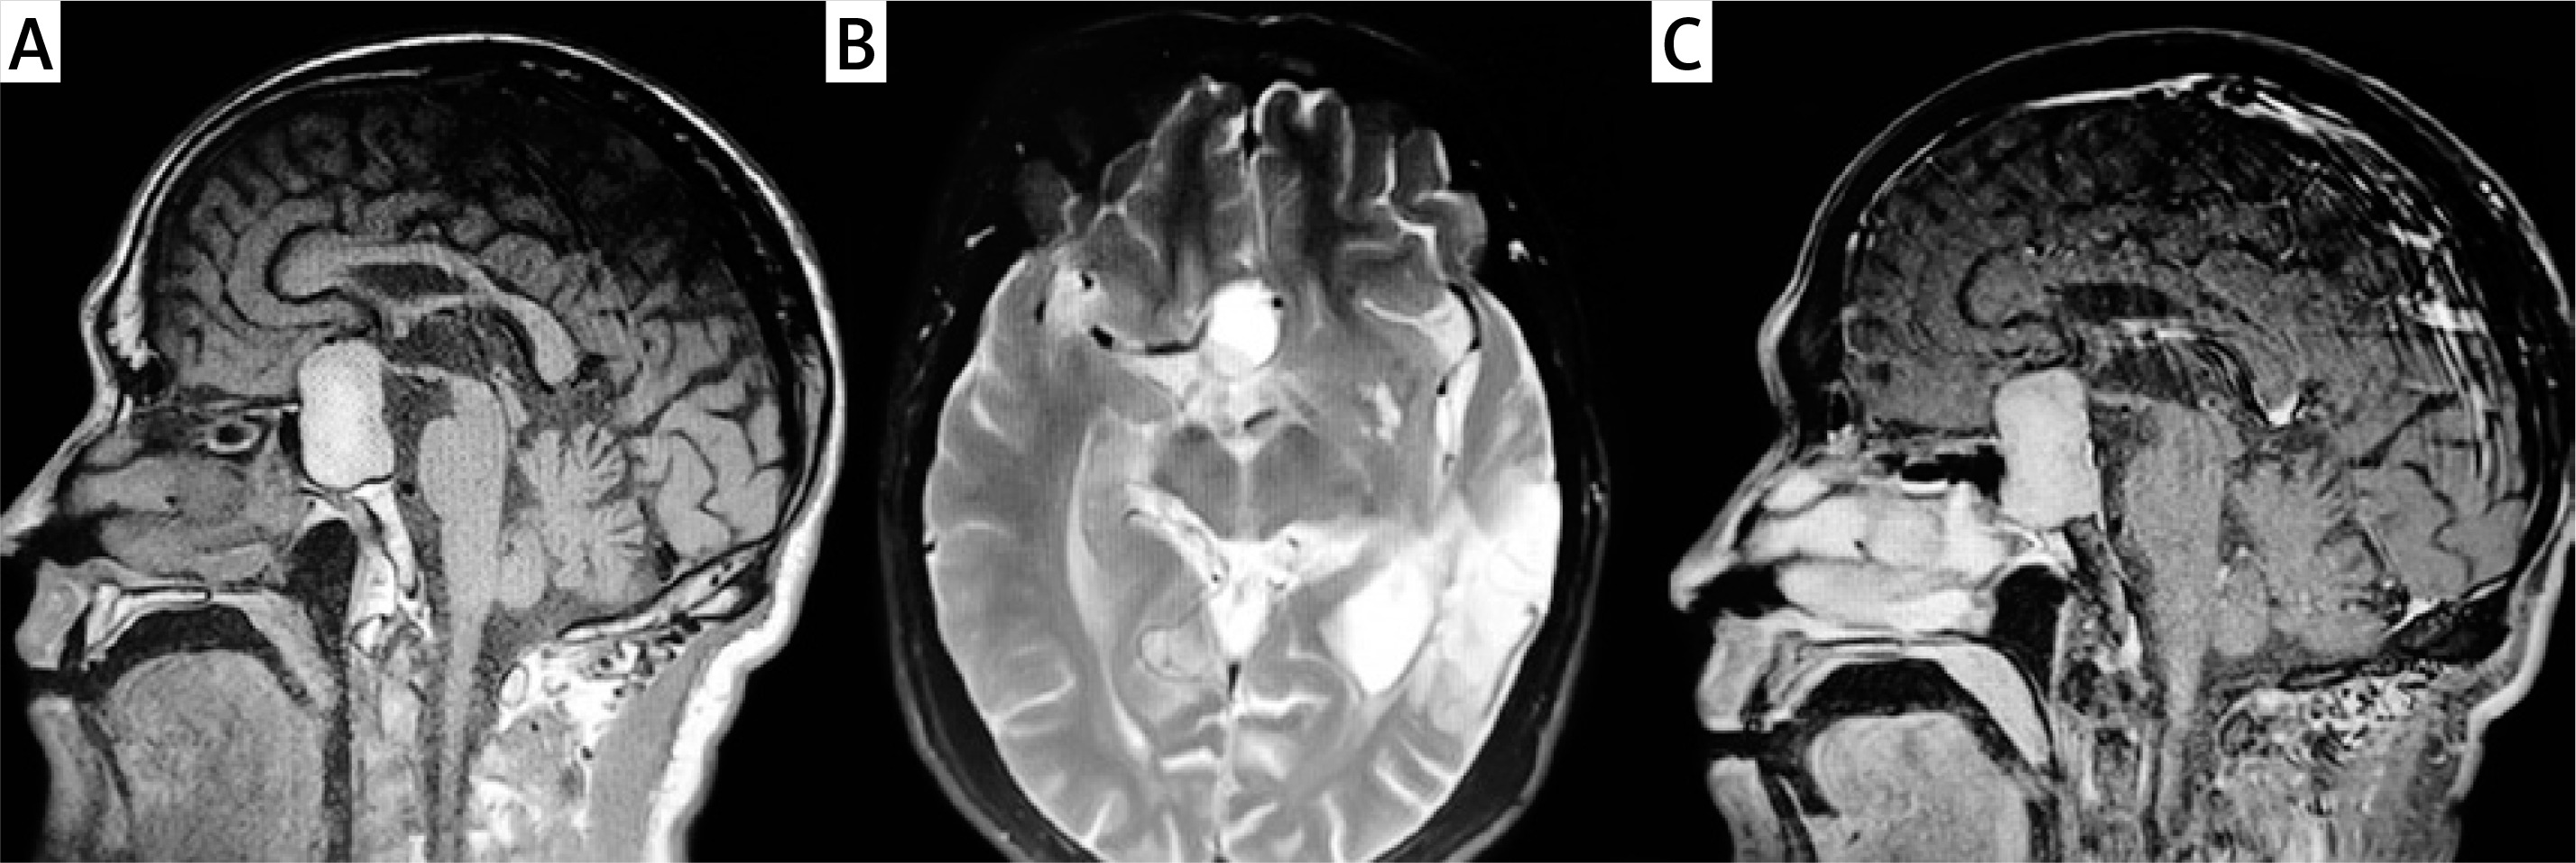

Imaging: MRI revealed a sellar and suprasellar mass measuring 4.0 × 1.5 × 2.0 cm. T1- and T2-weighted images showed hyperintense and hypointense signals respectively. Gadolinium enhancement showed uniform enhancement. The normal pituitary gland had disappeared, and only the posterior bright spot and pituitary stalk were seen (Figures 1 A–C).